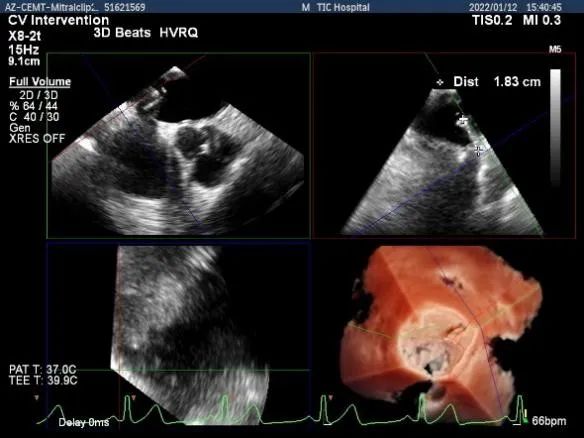

术前超声评估

术前超声诊断

Bicom:MR(重度),返流束宽12mm,返流面积10.3cm2,PISA法定量EROA:

0.77cm2,Rvol:115ml,RF:35%,r:12mm。

二尖瓣返流频谱呈全收缩期

肺静脉血流频谱呈收缩期反向

3D MV View:二尖瓣AC区为主(累及部分1区)脱垂并腱索断裂

3D-color MV view:大量返流,主要来源于AC区

Qlab软件勾画估测瓣口面积约:6.89cm2

二尖瓣口平均跨瓣压差:3mmHg

TEE Bicom view:二尖瓣AC区为主(累及部分1区)脱垂并腱索断裂。

Color-view:大量返流,主要来源于AC区